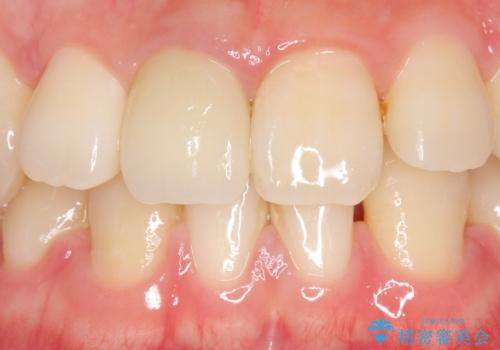

- 右上1番目の前歯の変色が気になるといらっしゃった方の症例です。

再根管治療後、オールセラミッククラウンによる補綴を行いました。

今回用いたオールセラミッククラウンはジルコニアフレームという白い素材の上にセラミックを盛っているため、審美性が非常に高いのが特徴です。